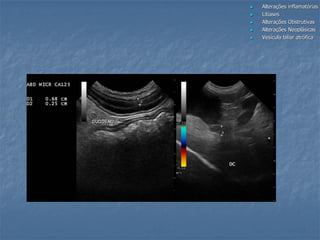

 Alterações inflamatórias Colangiohepatite,

Colecistite, Mucocele

 Litíases

 Alterações Obstrutivas

 Alterações Neoplásicas

 Vesícula biliar atrófica